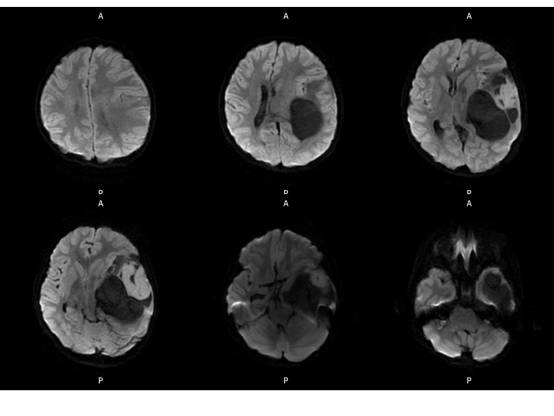

MR平扫及增强示:

MR

左侧颞叶见大块状等长T1等长T2异常信号,FLAIR呈高新,DWI(b=1000)实质部分呈稍高信号,ADC实质部分呈等信号,边界尚清,周围脑实质受压。注入GD-DTPA后病变实质部分呈明显强化。